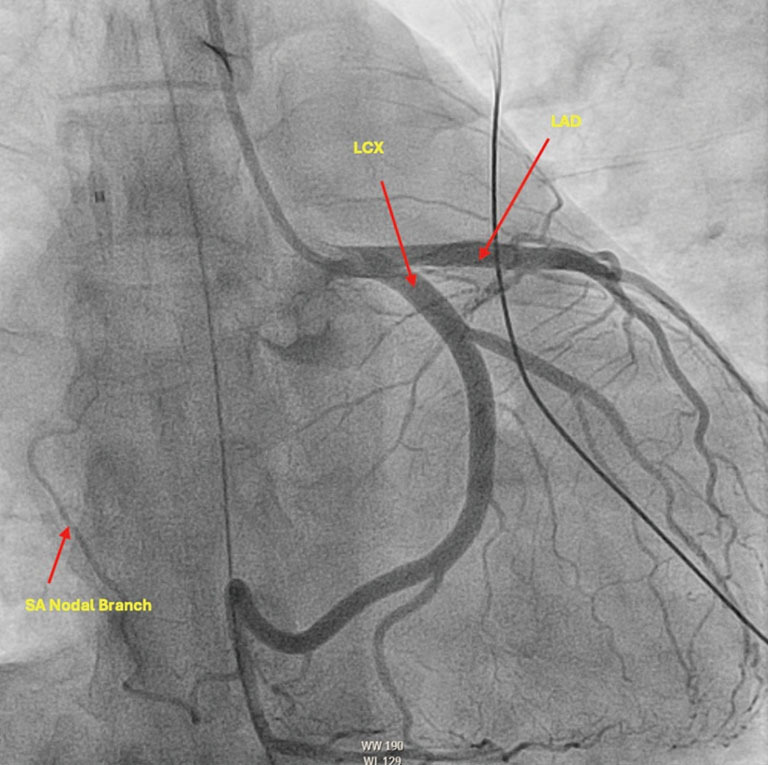

Case description: This report describes a 36-year-old female without prior cardiac history who presented in ventricular fibrillation (VF) electrical storm. While she lacked significant electrolyte abnormalities or ischemia to explain etiology of electrical storm, she incidentally had variant coronary anatomy noted on angiography. After thorough consideration of possible etiologies of storm, selective serotonin reuptake inhibitor (SSRI) intoxication was the most highly suspected etiology. Regarding management of her hemodynamically unstable electrical storm, she was treated with lidocaine, amiodarone, as well as mechanical circulatory support devices including extracorporeal membrane oxygenation (ECMO) and intra-aortic balloon pump (IABP). The patient ultimately was decannulated from ECMO, had IABP removal, and achieved recovery of ejection fraction (EF) to baseline. She was not offered ICD as the etiology of her cardiac arrest was reversable. She was discharged with recommendation to discontinue SSRI and follow up with psychiatry regarding SSRI overdose.